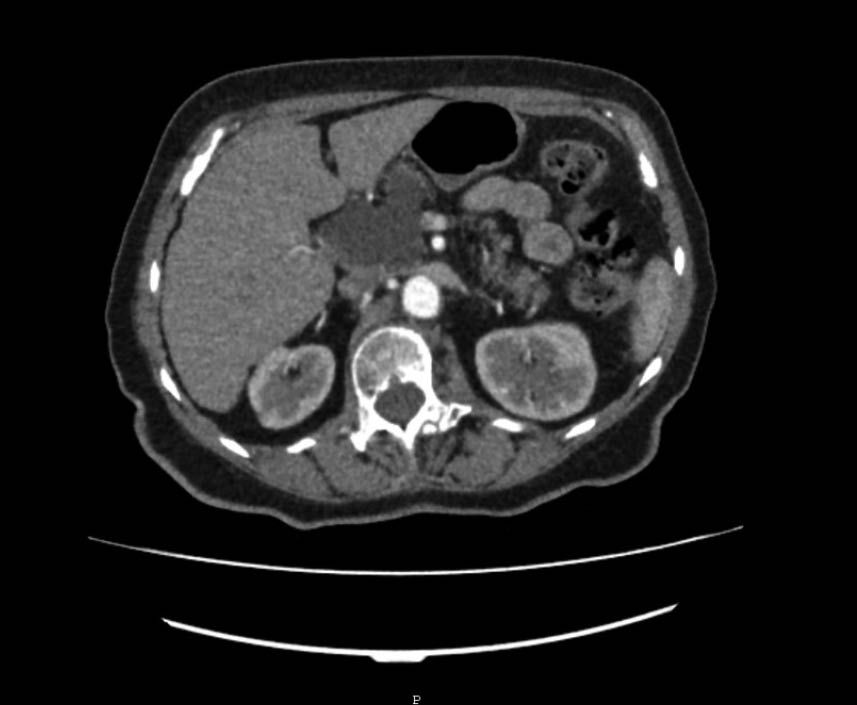

Seröses Zystadenom (SCN) – Abb. 1.A & 2.D

Abb. 1A

Repräsentative Abbildungen zu Bildgebungsverfahren von zystischen Pankreasläsionen: (A) CT-Scan eines serösen Zystadenoms des Pankreas (B) MRT-Scan einer Pankreas-assoziierten solid-pseudopapillären Neoplasie (C) EUS-„Image“ einer intrapankreatischen muzinös-zystischen Neoplasie